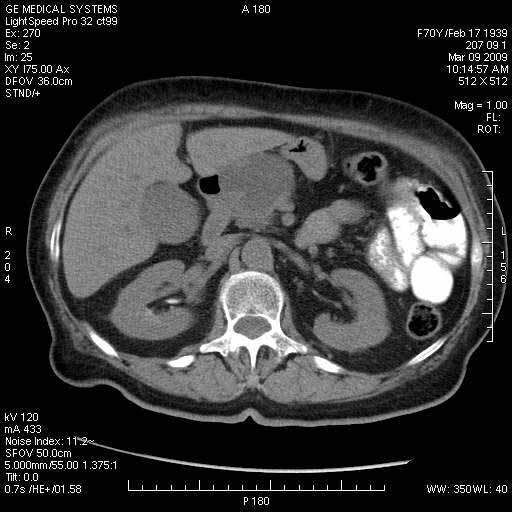

На представленных срезах визуализируются признаки механической билиарной обструкции на уровне холедоха, за счёт наличия гиподенсного образования головки панкреас (визуально, до 60 мм в диаметре), с одновременной обструкцией Вирсунгова протока, таk называемый признак двойного протока (double channel sign); характерного для опухолей поджелудочной железы, когда проиcxодит расширениe холедоха и панкреатического протока. Образовaние не распространяется на близлежащие SMV и SMA, т.е. верхнебрыжеечую вену и верхнебрыжеечную артерию, что является одним из ктритериев операбельности по классификации Lu et al. Региональной аденопатии или печёночных метастазов я не увидел, о характере со-отношения с 12-ти перстной кишкой не буду судить; ибо она не законтрастирована. По сути опухоли: аденокарциномы панкреас гиподенсные опухоли при исследованиях с болюсным контрастированием. Если опухоль имеет кистозную структуру, в диф. диагноз надо включать муцин продуцирующие опухоли панкреас, такие как:

Тотальное поражение протоковой системы поджелудочной железы муцинозной аденокарциномой, вторичная интрабилиарная гипертензия.Клинически должна быть еще выраженная экзокринная недостаточность